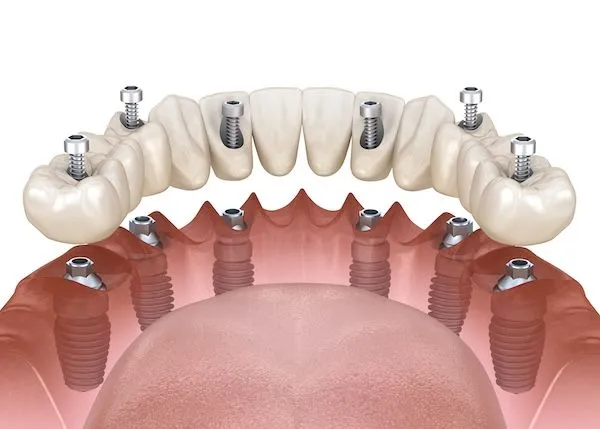

В большинстве случаев всё, что потребуется пациенту, это установка только шести имплантов. Это даст стоматологу возможность поставить несъёмный протез. В таком случае пациент будет чувствовать себя совершенно комфортно — его искусственные зубы будут так же функциональны, как и родные.

Помимо этого, возможна имплантация по другой методике. Используя её, можно поставить несъёмные зубные протезы даже на челюсть, на которой полностью удалены или утрачены зубы. При этом всё, что потребуется сделать, это установить четыре искусственных зуба.